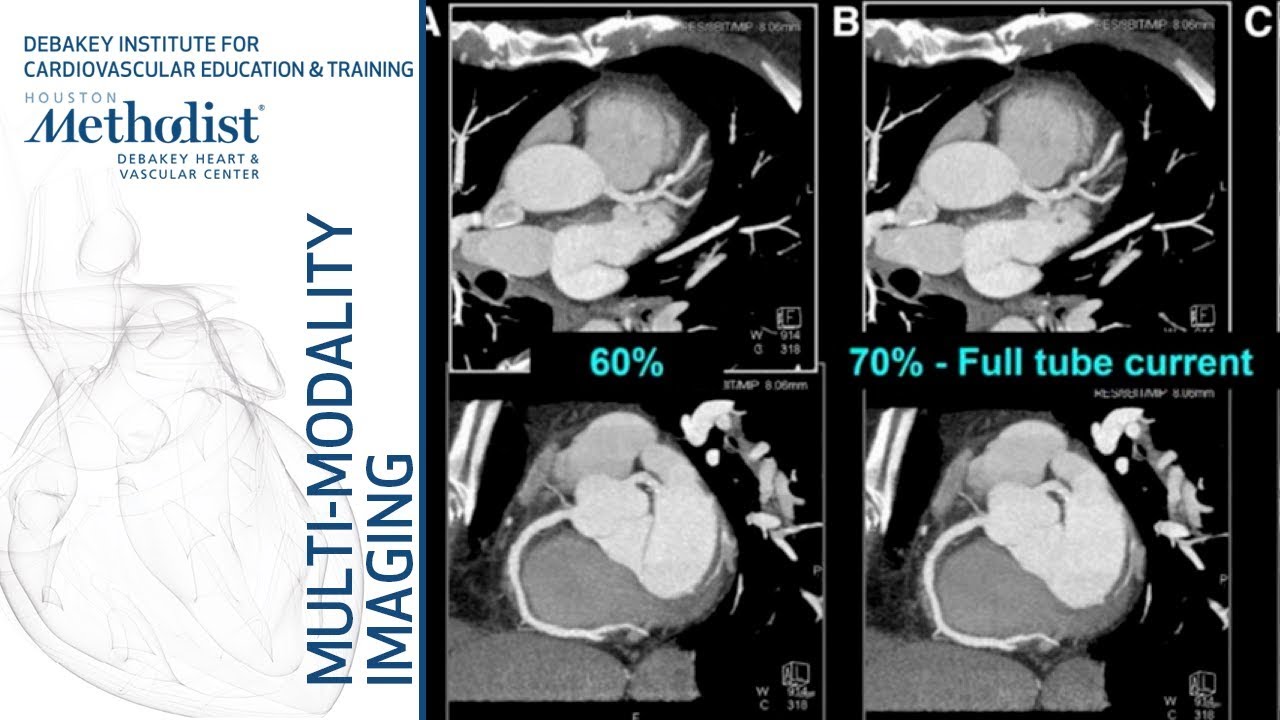

the on the right here we see the white arrows pointing to two areas of stenosis in the coronary arteries two areas that show that dye is kind of cut off is kind of blank for a moment indicating that there's not much blood there's not much fluid passing through the arteries at the point that the arrow is indicating and lastly we have cardiac CT CT is computed tomography and cardiac is obviously computed tomography of the heart which is a more complicated x-ray it's not quite as simple as a normal chest x-ray it's a series of x-rays

that are that are put together by a computer to produce an image and can also be used to produce a three-dimensional image cardiac CT is best to assess the extent of coronary stenosis so we can identify coordinate coronary stenosis best using cardiac catheterization we can we can assess the extent of stenosis we can get a higher resolution picture and see just how bad that artery is being as being clogged up using cardiac CT cardiac CT is also good to look at the thoracic aorta so if we have any kind of a or two problems such

as an aortic dissection cardiac CT can identify that the benefit of cardiac CT is that it's less invasive than catheterization you're not actually putting anything into the body and you can also produce a three-dimensional model which is something that catheterization cannot do and the drawbacks of CT are a pretty intense radiation exposure more so than check stray chest x-rays and more so than MRIs and of course to get some some pretty images you usually have to use contrast that can damage the kidneys so that's all we have for these imaging modalities of the heart I